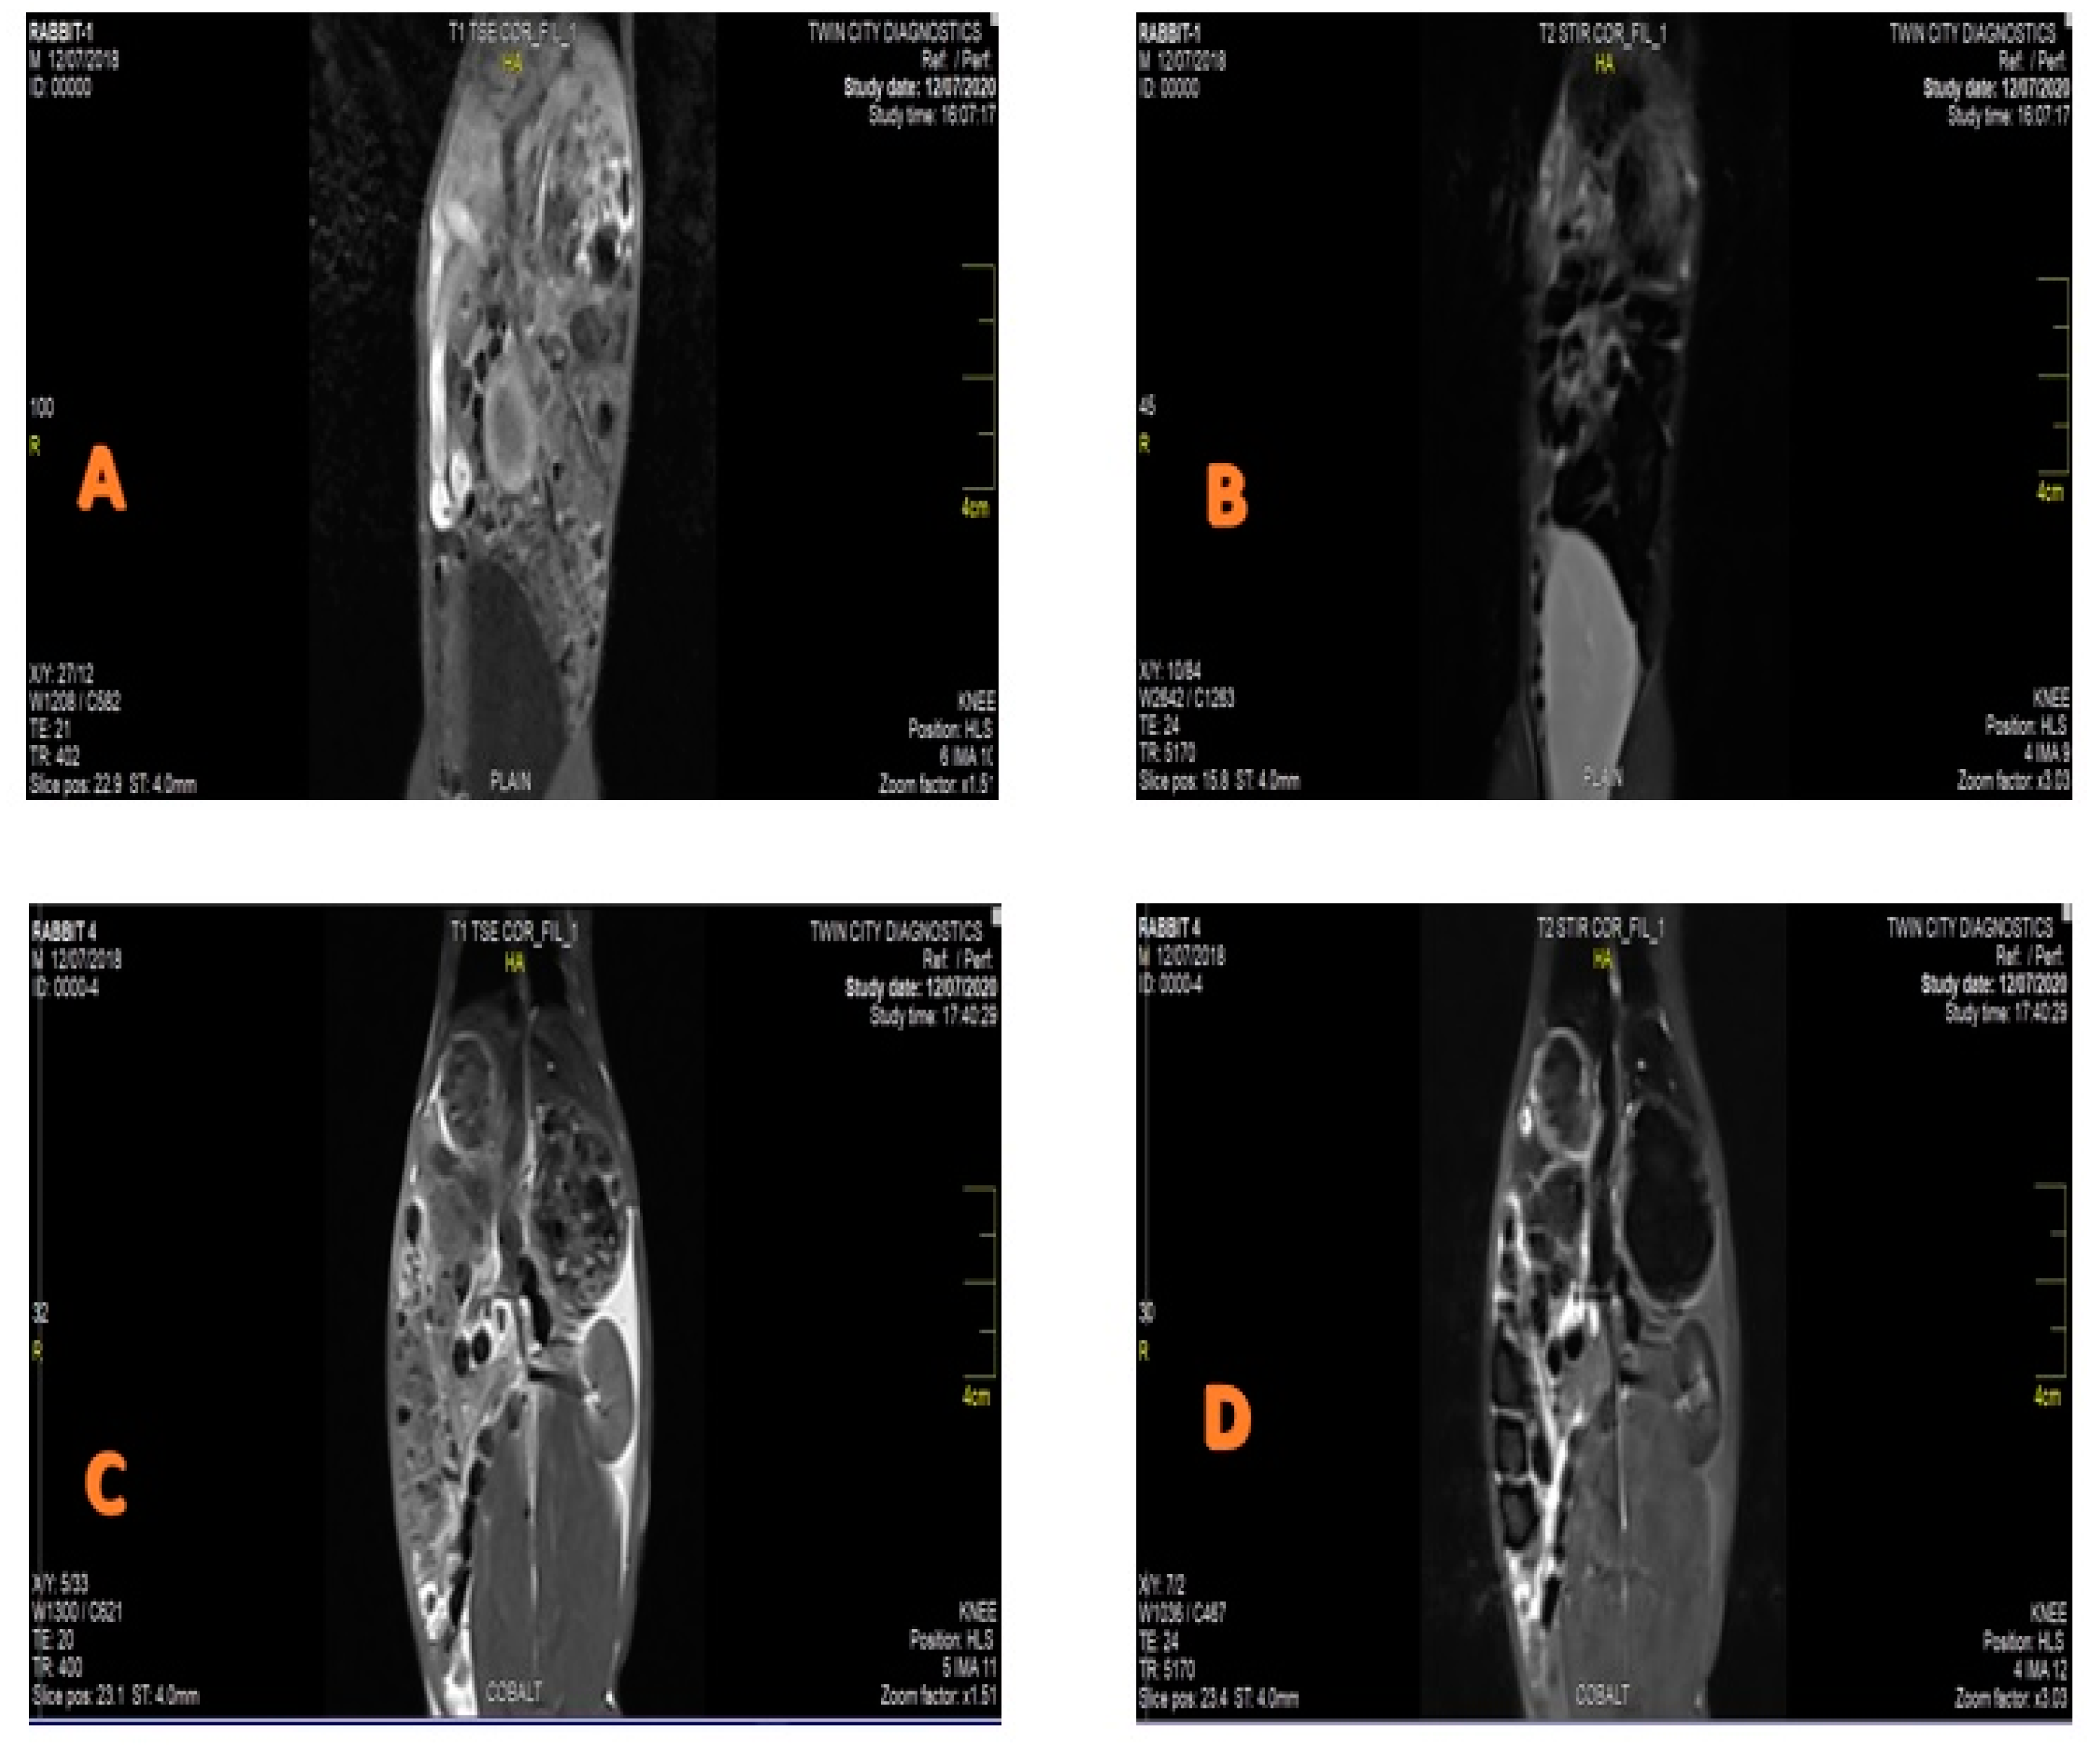

3.2. MRI Contrast Agent and Relaxivity